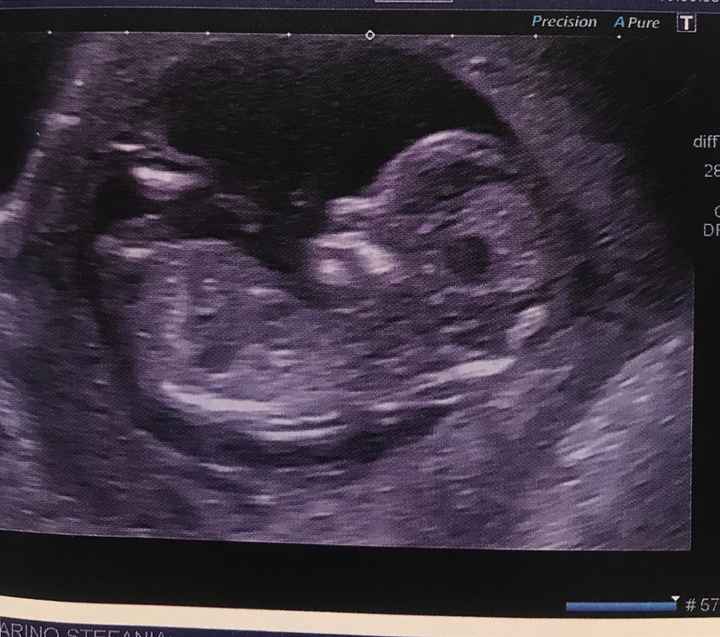

Mancano ancora tantissime settimane alla morfologica, che avrò il 15 Luglio, mi ritrovo spesso a fantasticare se sarà Filippo o Lucrezia, io mi sento maschio ma non si sa mai.

Mi affido a voi esperte di Nub Theory, cosa dite maschio o femmina??